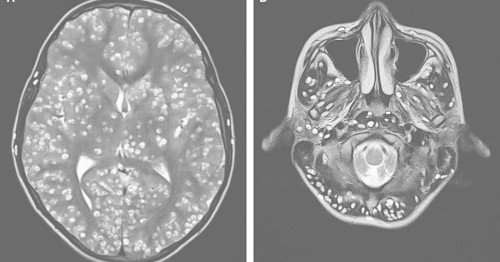

See what happens when tapeworms infest your brain